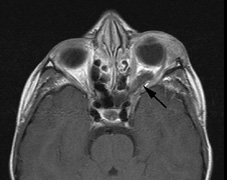

Growth of a plexiform neuroma may be directed posteriorly, infiltrating orbital tissues and involving the bony walls. Congenital plexiform neuromas of the orbit are often associated with absence of the sphenoid wing (Fig. 5). Intracranial pulsation can be transmitted to the orbit causing pulsatile proptosis or enophthalmos.57–59 Plexiform neuromas of the lid and orbit are difficult to treat; complete excision is difficult and potentially disfiguring. The tumors are vascular and may bleed copiously at surgery. They are not radiosensitive and there is also risk of inducing malignant transformation. Trials with antiangiogenic chemotherapeutic agents (thalidomide, interferon alpha) and mitotic-signaling pathway blockers (inhibition of Ras by Farnesyl protein tranferase inhibitor) are in progress.60,61

Optic pathway gliomas arise from the astrocytes of the optic nerve. Most are pilocytic astrocytomas and typically remain intradural, extending in the subdural space. Malignant transformation is rare. There appear to be two growth patterns62:

- Perineural growth pattern, correlating with a diagnosis of NF1. The tumor expands in the subarachnoid

space and the optic nerve is compressed as a central ribbon. On

T2-weighted MRI, this may be seen as a low-intensity core with surrounding

high-intensity rim. Increased tortuosity of the optic nerve is also

associated with this growth pattern (Fig. 5).63

- Optic glioma (Fig. 5)